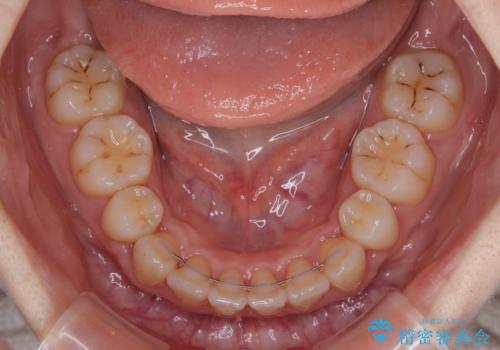

順調に治療が進み、2年弱で想定していたとおりの仕上がりにて治療を終えることができました。